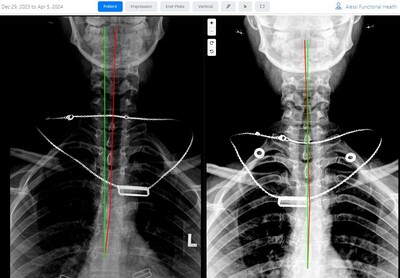

Results You Can See... and Feel!